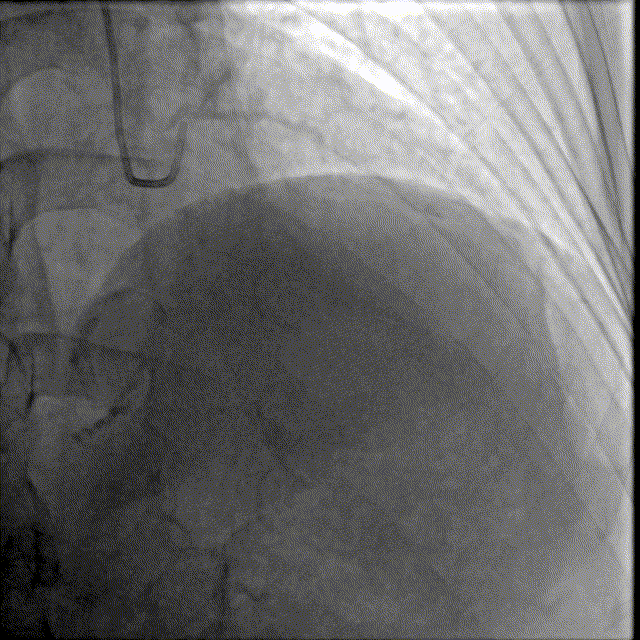

选择EBU指引导管,以2.0预扩张球囊及2.5×12mm耐高压球囊预扩前降支近段病变,可见不同程度的球囊膨胀欠佳。